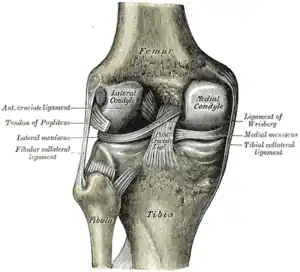

Ligaments

The ligaments surrounding the knee joint offer stability by limiting movements and, together with the menisci and several bursae, protect the articular capsule.[19]

Intracapsular

The knee is stabilized by a pair of cruciate ligaments. These ligaments are both extrasynovial, intracapsular ligaments.[20] The anterior cruciate ligament (ACL) stretches from the lateral condyle of femur to the anterior intercondylar area.[13] The ACL prevents the tibia from being pushed too far anterior relative to the femur.[13] It is often torn during twisting or bending of the knee.[21] The posterior cruciate ligament (PCL) stretches from medial condyle of femur to the posterior intercondylar area. This ligament prevents posterior displacement of the tibia relative to the femur.[13] Injury to this ligament is uncommon but can occur as a direct result of forced trauma to the ligament.

The transverse ligament stretches from the lateral meniscus to the medial meniscus. It passes in front of the menisci. It is divided into several strips in 10% of cases.[10]: 208 The two menisci are attached to each other anteriorly by the ligament.[22] The posterior (of Wrisberg) and anterior meniscofemoral ligaments (of Humphrey) stretch from the posterior horn of the lateral meniscus to the medial femoral condyle. They pass anterior and posterior to the posterior cruciate ligament respectively.[13][10]: 208 The meniscotibial ligaments (or "coronary") stretches from inferior edges of the menisci to the periphery of the tibial plateaus.

Extracapsular

The patellar ligament connects the patella to the tuberosity of the tibia. It is also occasionally called the patellar tendon because there is no definite separation between the quadriceps tendon (which surrounds the patella) and the area connecting the patella to the tibia.[23] This very strong ligament helps give the patella its mechanical leverage[24] and also functions as a cap for the condyles of the femur. Laterally and medially to the patellar ligament, the lateral and medial retinacula connect fibers from the vasti lateralis and medialis muscles to the tibia. Some fibers from the iliotibial tract radiate into the lateral retinaculum and the medial retinaculum receives some transverse fibers arising on the medial femoral epicondyle.[10]: 206

The medial collateral ligament (MCL a.k.a. "tibial") stretches from the medial epicondyle of the femur to the medial tibial condyle. It is composed of three groups of fibers, one stretching between the two bones, and two fused with the medial meniscus. The MCL is partly covered by the pes anserinus and the tendon of the semimembranosus passes under it.[10]: 206 It protects the medial side of the knee from being bent open by a stress applied to the lateral side of the knee (a valgus force).[10]: 206

The lateral collateral ligament (LCL a.k.a. "fibular") stretches from the lateral epicondyle of the femur to the head of fibula. It is separate from both the joint capsule and the lateral meniscus.[10]: 206 It protects the lateral side from an inside bending force (a varus force). The anterolateral ligament (ALL) is situated in front of the LCL.

Lastly, there are two ligaments on the dorsal side of the knee. The oblique popliteal ligament is a radiation of the tendon of the semimembranosus on the medial side, from where it is direct laterally and proximally. The arcuate popliteal ligament originates on the apex of the head of the fibula to stretch proximally, crosses the tendon of the popliteus muscle, and passes into the capsule.[10]: 206

Illustrations

Cruciate ligaments

Left knee-joint from behind, showing interior ligaments.